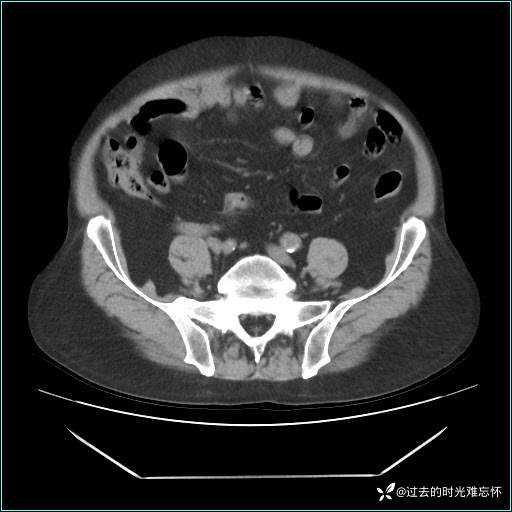

患者男,71 岁,因「反复腹痛腹胀 1 月」入院。

现病史:患者 1 月前无明显诱因下出现腹痛腹胀症状,腹痛呈隐痛,当时未予以重视,后症状有所加重,常在进食辛辣刺激油腻等食物后出现腹痛,口服药物治疗症状能得到控制,病情控制一般。现为求诊治来我院,拟“腹痛”入院。病程中患者神志清楚,精神一般,无咳嗽咳痰,无恶心呕吐,近期体重无明显变化。